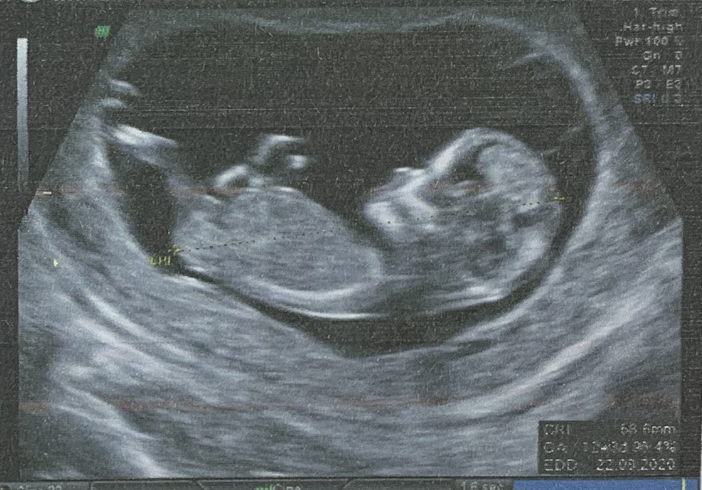

Смотрите фото прилагаю .

Это фото я кидала и многие предположили о нему девочку

( мне кажется тут пуповина между ног)